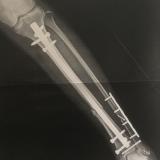

フォロー ブログを報告 登録ID 1934543 タイトル 交通事故で足の切断の危機から毎日1万歩!歩けるまでの挑戦 URL http://chikako259.blog.fc2.com/ カテゴリ リハビリテーション (69位/90人中) 整骨・接骨 (72位/93人中) リハビリテーション科 (9位/14人中) 紹介文 足の切断の危機から半年の入院を経て歩けるようになるまでの軌跡を綴ります。 登録:2017年09月(8年) 1 記事一覧